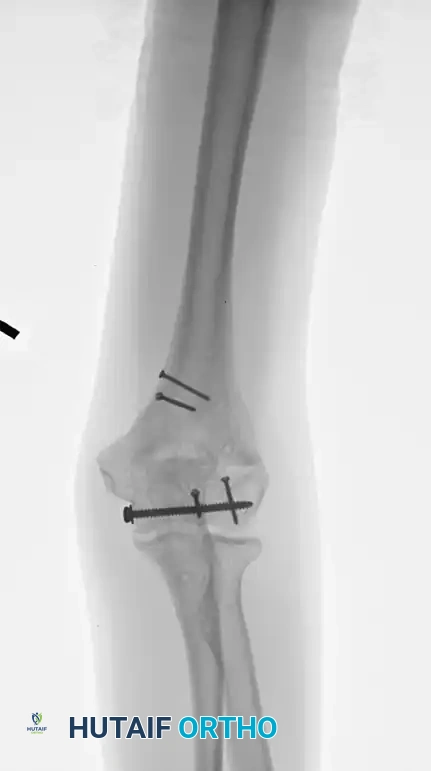

Supracondylar fracture intraarticular

Preoperative imaging of a supracondylar fracture with intraarticular extension.

Fixation 90-90

Fixation achieved with 90-90 locked plates through an olecranon osteotomy approach.

After hardware removal

Radiograph demonstrating a healed fracture after the removal of symptomatic hardware.